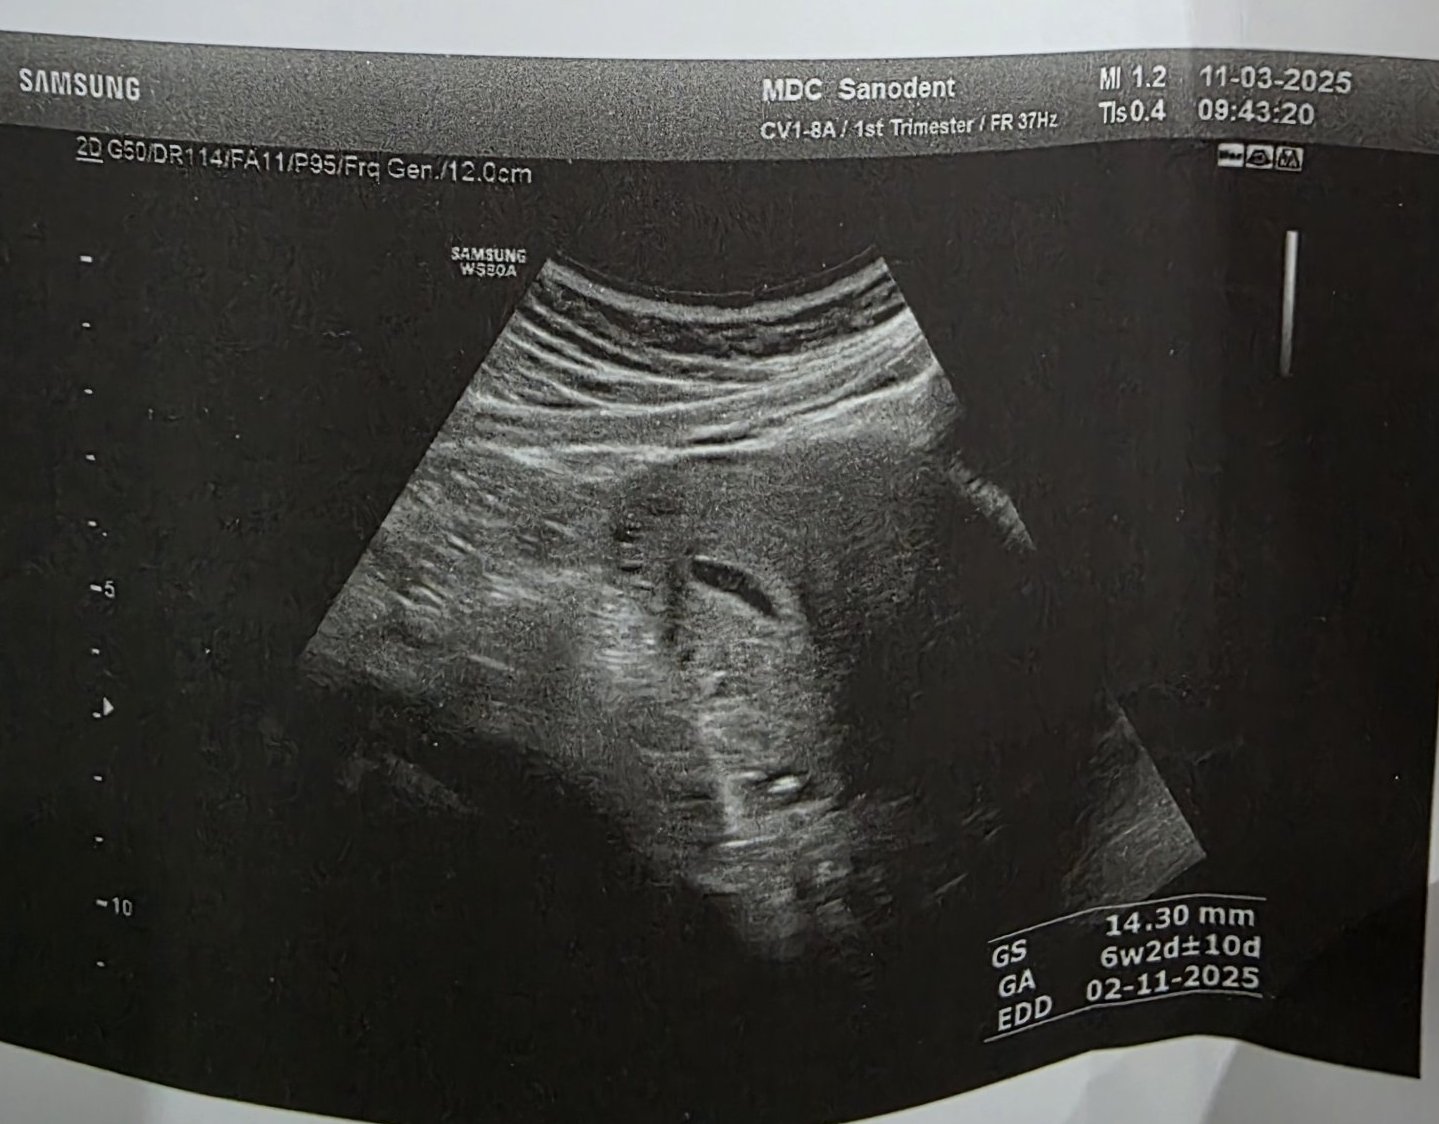

Какво представлява изображението от ехографията на 5-седмична и 2-дневна бременност?

Какво представлява изображението от ехографията на 5-седмична и 2-дневна бременност?

Кога обикновено може да се види ембрионът на ултразвукова снимка?

Какво представляват черните точки в матката на ехографската снимка?